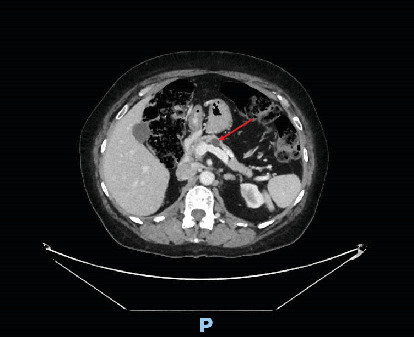

Urologists are commonly referred patients with retroperitoneal lesions and masses arising from or involving the kidney. In this case, the patient had a retroperitoneal mass identified on imaging which was initially concerning for a cystic renal neoplasm, but it was clearly distinct from all surrounding structures. Pathology found the very uncommon and unexpected diagnosis of a mucinous cystic neoplasm (MCN) with ovarian-type stroma suspected to have arisen from the pancreas. MCNs are lesions that most commonly arise in the ovaries, but less often can arise in extraovarian tissues. Of these extraovarian MCNs, primary retroperitoneal MCNs are exceedingly rare masses with some similarity to their pancreatic and ovarian counterparts. We present a case of an MCN found in the retroperitoneum and initially mistaken for a cystic renal mass, with histological markers and a concomitant pancreatic cyst that suggests possible pancreatic origin. Interestingly, no literature has described pancreatic MCNs without invasive features that have been found in the retroperitoneum without any formal tissue connection to the pancreas. The pathogenesis of retroperitoneal MCNs is still unknown, and as a result, the optimal treatment strategy is unclear.